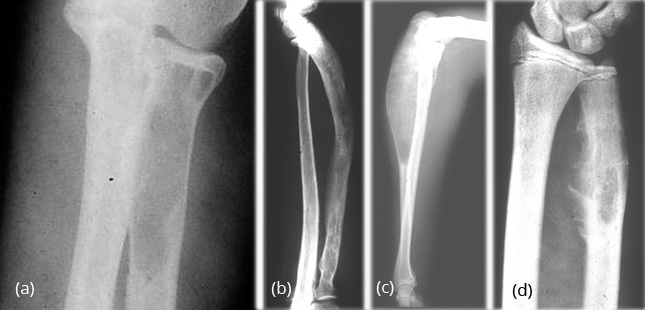

In the radius and ulna, cystic lesions may be noted or diffuse sclerosis with deformity (Figure 14a,b,c,d).

Figure 14: FD – (a, b) Radius, (c, d) Ulna In the hands, monostotic is rare.

Fibro osseous dysplasia (ossifying fibroma) (Figure 29)

- Almost exclusively in tibia with anterior bowing

- Lesion begins in cortex

- Usually seen in children <10 years

Figure 29: Ossifying fibroma – Note the extensive changes in the tibia simulating FD. Anterior bowing is characteristic.